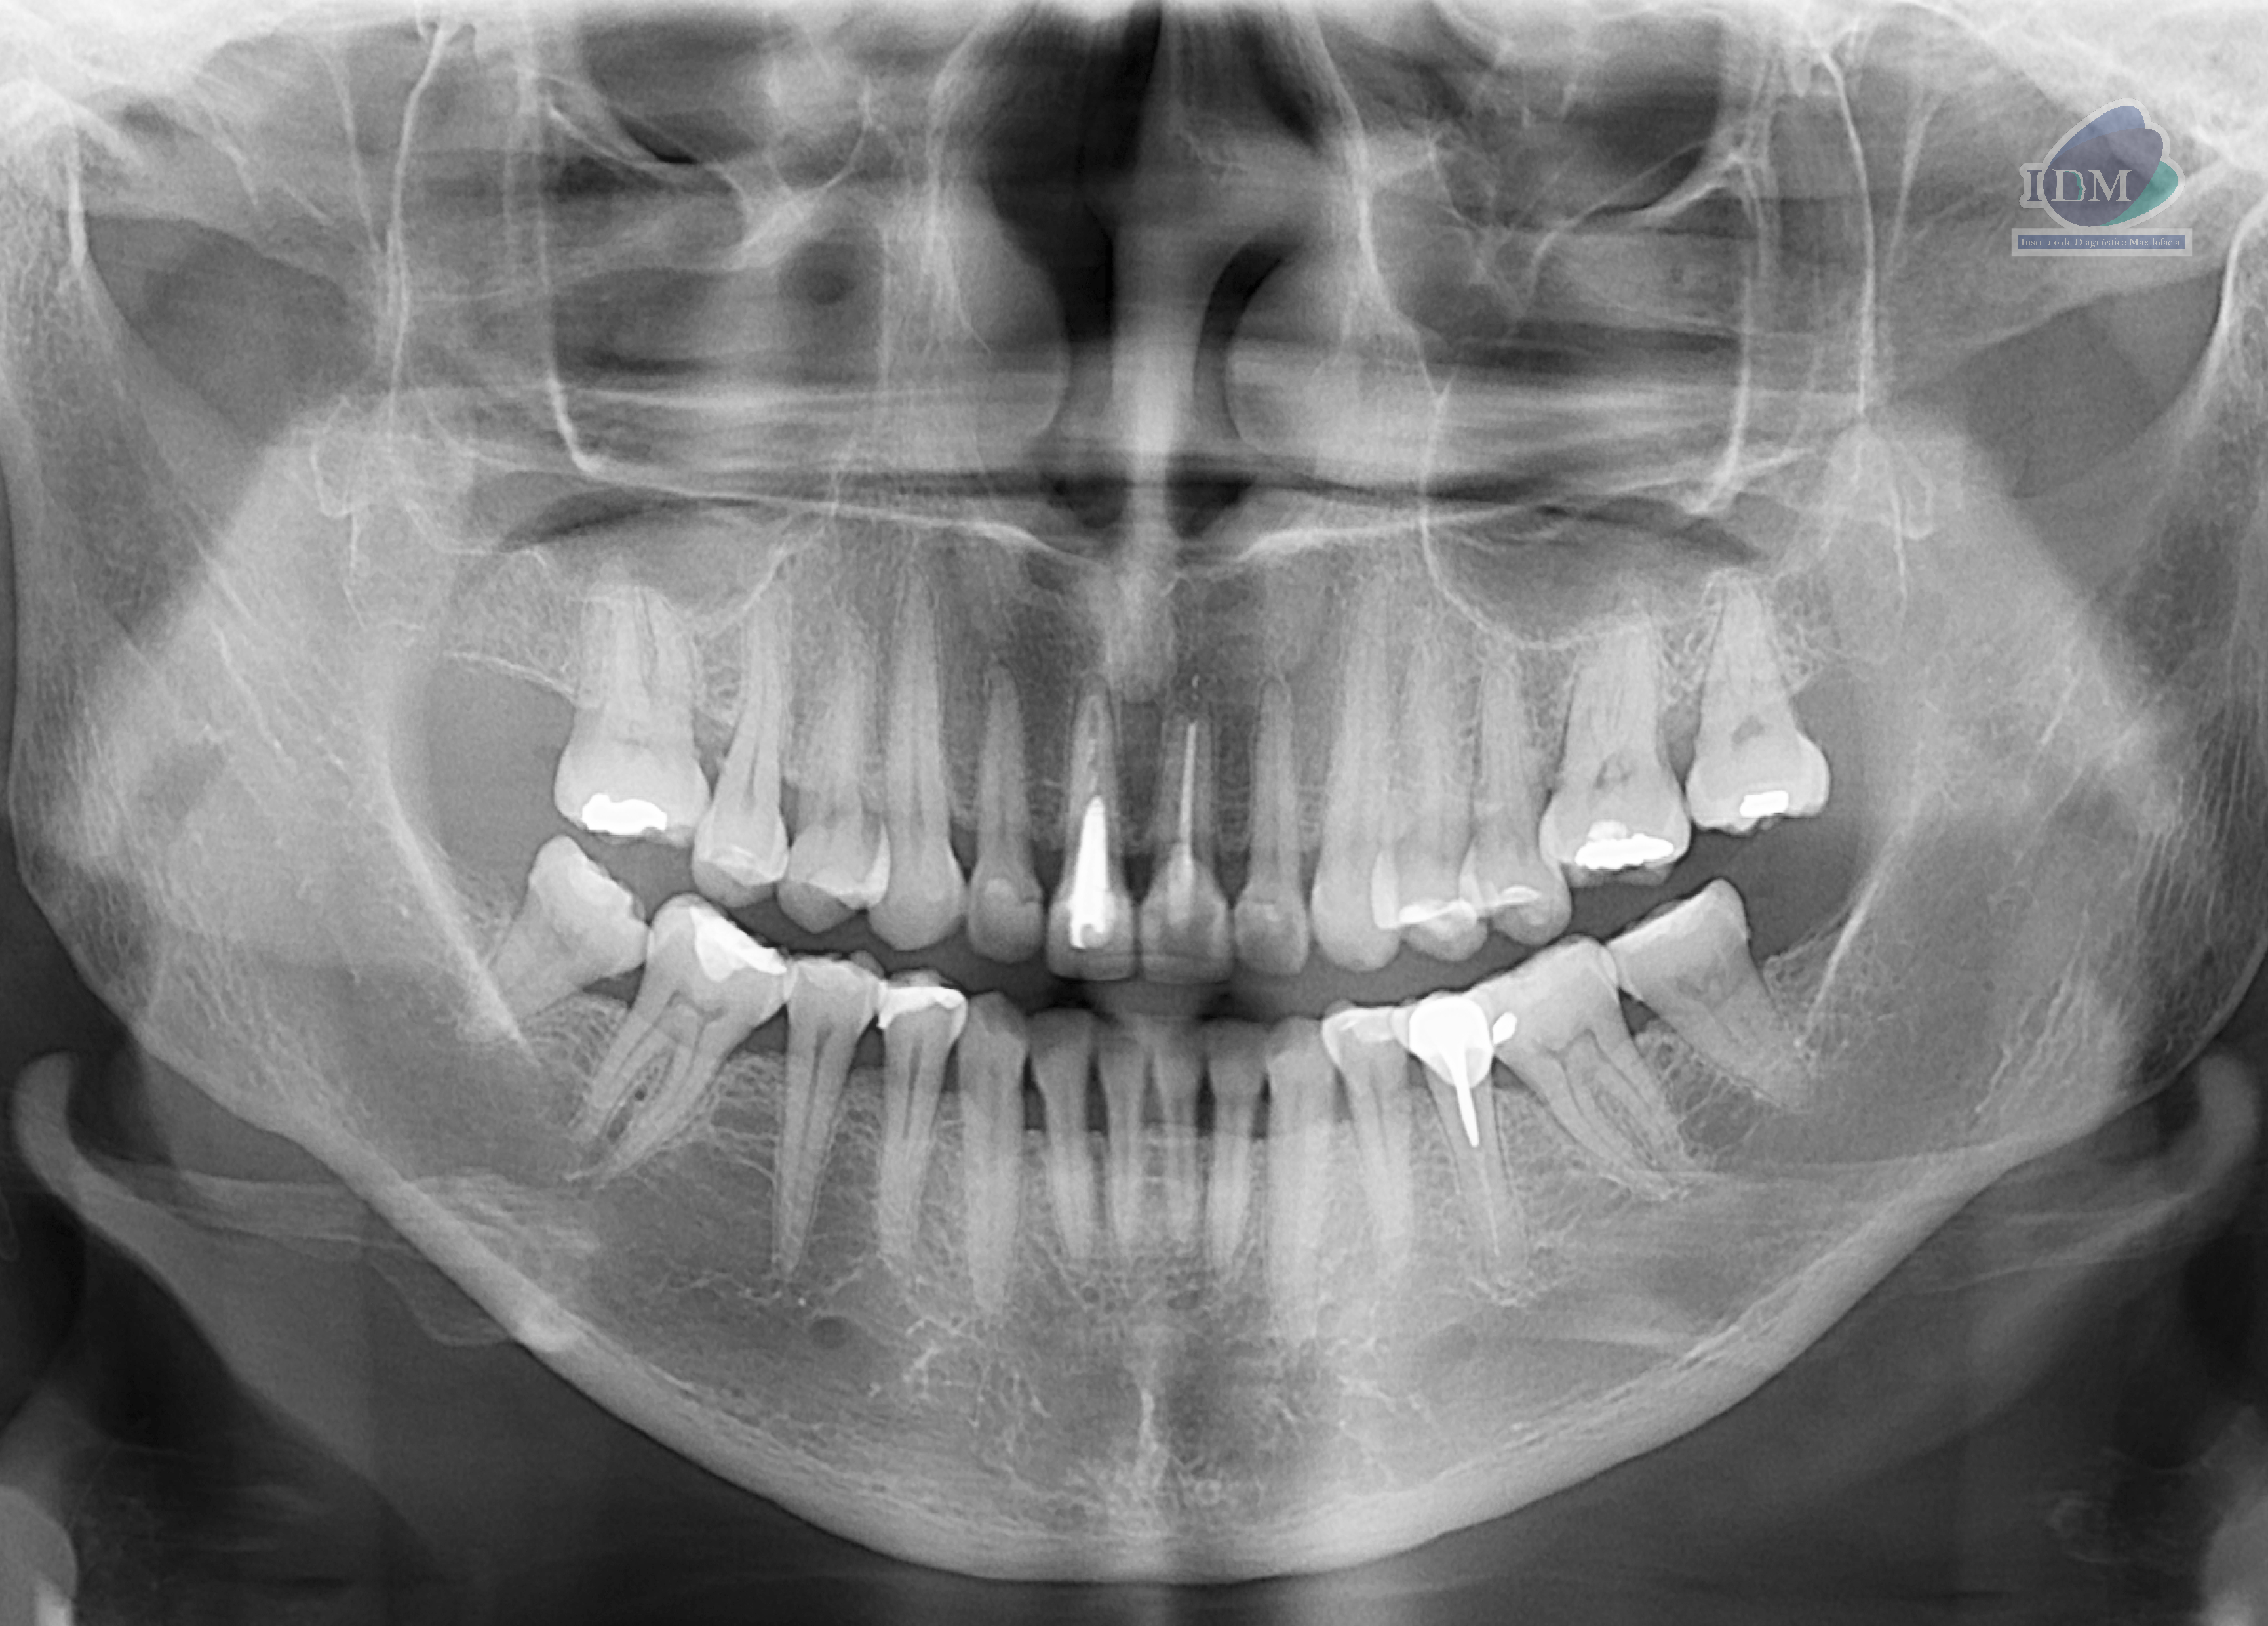

En la radiografía panorámica (Figura 1), se observa pieza 11 con corona protésica, espigo intrarradicular y obturación parcial de conducto y pieza 21 con corona protésica, obturación de conducto y disminución de la densidad en tercio apical.

Radiografia Panorámica